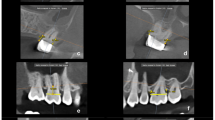

The etch-and-rinse and bonding procedure was performed according to the manufacturer’s instruction. The root canal and the coronal tooth surface were etched with 36% phosphoric acid (Conditioner 36, Dentsply DeTrey) for 15 s. After water rinsing and air-drying, the adhesive was applied and left for 20 s (XP Bond, Self-cure Activator, Dentsply DeTrey, 1:1 ratio, mixed for 2 s). A glass fibre post (size 2 (red), Ø 1.25 mm, X-Post, CTS, Dentsply DeTrey) was treated with adhesive and was luted with core build-up material in a staged procedure using a dual curing core-and-post composite (Core-X™ flow, Dentsply DeTrey). The core was built up by means of a strip crown (upper central incisor, Frasaco, Tettnang, Germany) and polymerized from the incisal, palatal, and facial aspect for 20 s each. All teeth were prepared with a circumferential 0.8 mm shoulder and 6° convergence angle to meet all-ceramic crown requirements. To achieve an equal crown length, the core build-ups were similar in length for group I to III (4 mm) and for group IV (6 mm). The margin was located 2 mm below the core build-up in dentin to ensure proper ferrule design. Specimens were scanned with an intraoral scanner (Trios, 3Shape, Kopenhagen, Dänemark); models were milled out of polyurethan. Crowns were constructed digitally (Dental Designer, 3Shape, Copenhagen, Denmark), subsequently milled in wax (Organical Multi, R + K CAD/CAM, Berlin, Germany), transferred to lithium disilicate (IPS e.max, Ivoclar Vivadent, Schaan, Germany), and glazed (IPS e.max Ceram Glaze, Ivoclar Vivadent). Crown width was 2 mm incisally, 1.5 mm in the middle, and 0.8 mm at the preparation margin. Crown height was 8 mm, except in group IV (10 mm) (Figs. 1 and 2).

Implant-based restoration, group V

Dental implants (length 12 mm, diameter 4.1 mm, Straumann Bone Level, Freiburg, Germany) were restored with titanium alloy base (RC Variobase Abutment, diameter 4.5 mm, length 3.5 mm, Straumann, Germany) with lithium disilicate abutments (IPS e.max, Ivoclar Vivadent, Schaan, Liechtenstein). Twelve identical lithium disilicate abutments were modelled in wax (Dental Designer, 3Shape, Copenhagen), milled (Organical Multi, R + K CAD/CAM, Berlin), and transferred in lithium disilicate (IPS e.max, Ivoclar Vivadent). Abutment measures were equivalent to cores of group I. Abutments were luted on the alloy bases with self-adhesive luting composites (IPS E.max Abutment Solution Cem Kit, Ivoclar Vivadent). Abutments were screwed in with 35Ncm. Crowns were etched 20 s with fluoric acid (Vita Ceramics Etch, Vita, Bad Säckingen, Germany), cleaned with water and isopropanol, silanized (Monobond Plus, Ivoclar Vivadent, Schaan) for 60 s, and self-adhesively luted (SmartCem Dentsply DeTrey). Final light curing was performed for 20 s from each restoration side.

Loading protocol

Thermal and mechanical loading (TML) was performed (parameters: 6000 thermal cycles, 5 °C/ 55 °C, 2 min each cycle; dist. water; 1.2 × 106 mastication cycles with 50N) to simulate 5 years of clinical service [14]. The restorations were loaded under 135°, 3 mm below the incisal edge, on the palatal surface of the crown. After TCML, tooth mobility was measured three times for each specimen by means of a Periotest device perpendicular to tooth and implant axis (Periotest Classic, Medizintechnik Gulden, Germany). Specimens were statically loaded in a universal testing machine (Zwick 1446, Zwick, Ulm, Germany; v = 1 mm/min) until failure. Failure detection was set at a 10% loss of the maximum applied force. A 0.3-mm-thick tin foil was positioned between the steel piston and the palatal crown surface to reduce excessive stress concentrations (Fig. 3).

Specimens that failed early in TML were excluded from further analysis. Median fracture load ranged from 195 N (group IV) to 446 N (group V), with statistically significant differences between groups (p = 0.001). The same is also true (p = 0.002) when early TML failures were included in analysis and were assigned a static load of “Fmax = 0”. The pair-wise comparison showed significant differences between all tooth-based groups (I–IV) and the implant group V (p = 0.001) and surgical crown lengthening group IV compared to group I (p = 0.045), group II apical root resection (p = 0.001), and group III extrusion (p = 0.033), respectively. Inclusion of specimens of “Fmax = 0” did also reveal significant differences between the implant and all other groups (p = 0.002). Neither the comparison of fracture pattern frequency (p = 0.649) nor analysis of clinical judgement in “restorable” vs. “catastrophic” failures revealed statistically significant differences (p = 0.172) between the tooth-based groups. Due to its completely different nature, implant-borne restoration was not included in this analysis. All implants were capable to be re-restored (Fig. 4).

Table 1 provides detailed information about specimen mobility, effective root length, crown-to-root ratio, early failures during TML, load capability values, failure patterns and frequency, and their respective clinical judgement, i.e. when a re-restoration of the teeth would be clinical possible. Figure 5 displays the scatterplot of RCRR and Fig. 6 of maximum load capability after linear load testing (median values as bold line).